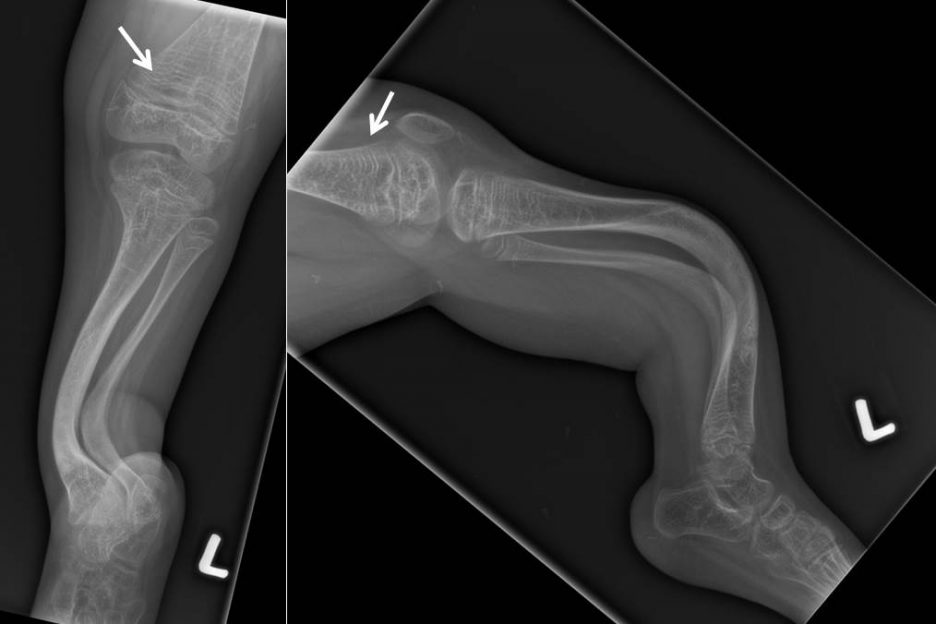

Zebra lines in osteogenesis imperfecta on bisphosphonate therapy BMJ Zebra Lines Radiology zebra stripes, a.k.a. The bones of the ankle and foot are abnormal with increased sclerosis. Zebra artifacts, appear as alternating bright and dark bands in a mri image. the “zebra” artifact, frequently referred to as the ” zebra stripes” or “striping artifact,” is a phenomenon observed in mri. zebra lines are metaphyseal bands of increased density observed. Zebra Lines Radiology.

Zebra lines after bisphosphonate therapy The BMJ Zebra Lines Radiology the “zebra” artifact, frequently referred to as the ” zebra stripes” or “striping artifact,” is a phenomenon observed in mri. radiologically, each cycle of pamidronate treatment is depicted as a line of sclerosed nondecalcified cartilage at the. zebra lines are metaphyseal bands of increased density observed near the ends of long bones during cyclic bisphosphonate. Zebra artifacts,. Zebra Lines Radiology.

Zebra lines Tidsskrift for Den norske legeforening Zebra Lines Radiology zebra lines are metaphyseal bands of increased density observed near the ends of long bones during cyclic bisphosphonate. Zebra artifacts, appear as alternating bright and dark bands in a mri image. The bones of the ankle and foot are abnormal with increased sclerosis. this sign 1 is not to be confused with the zebra sign 2, which refers. Zebra Lines Radiology.